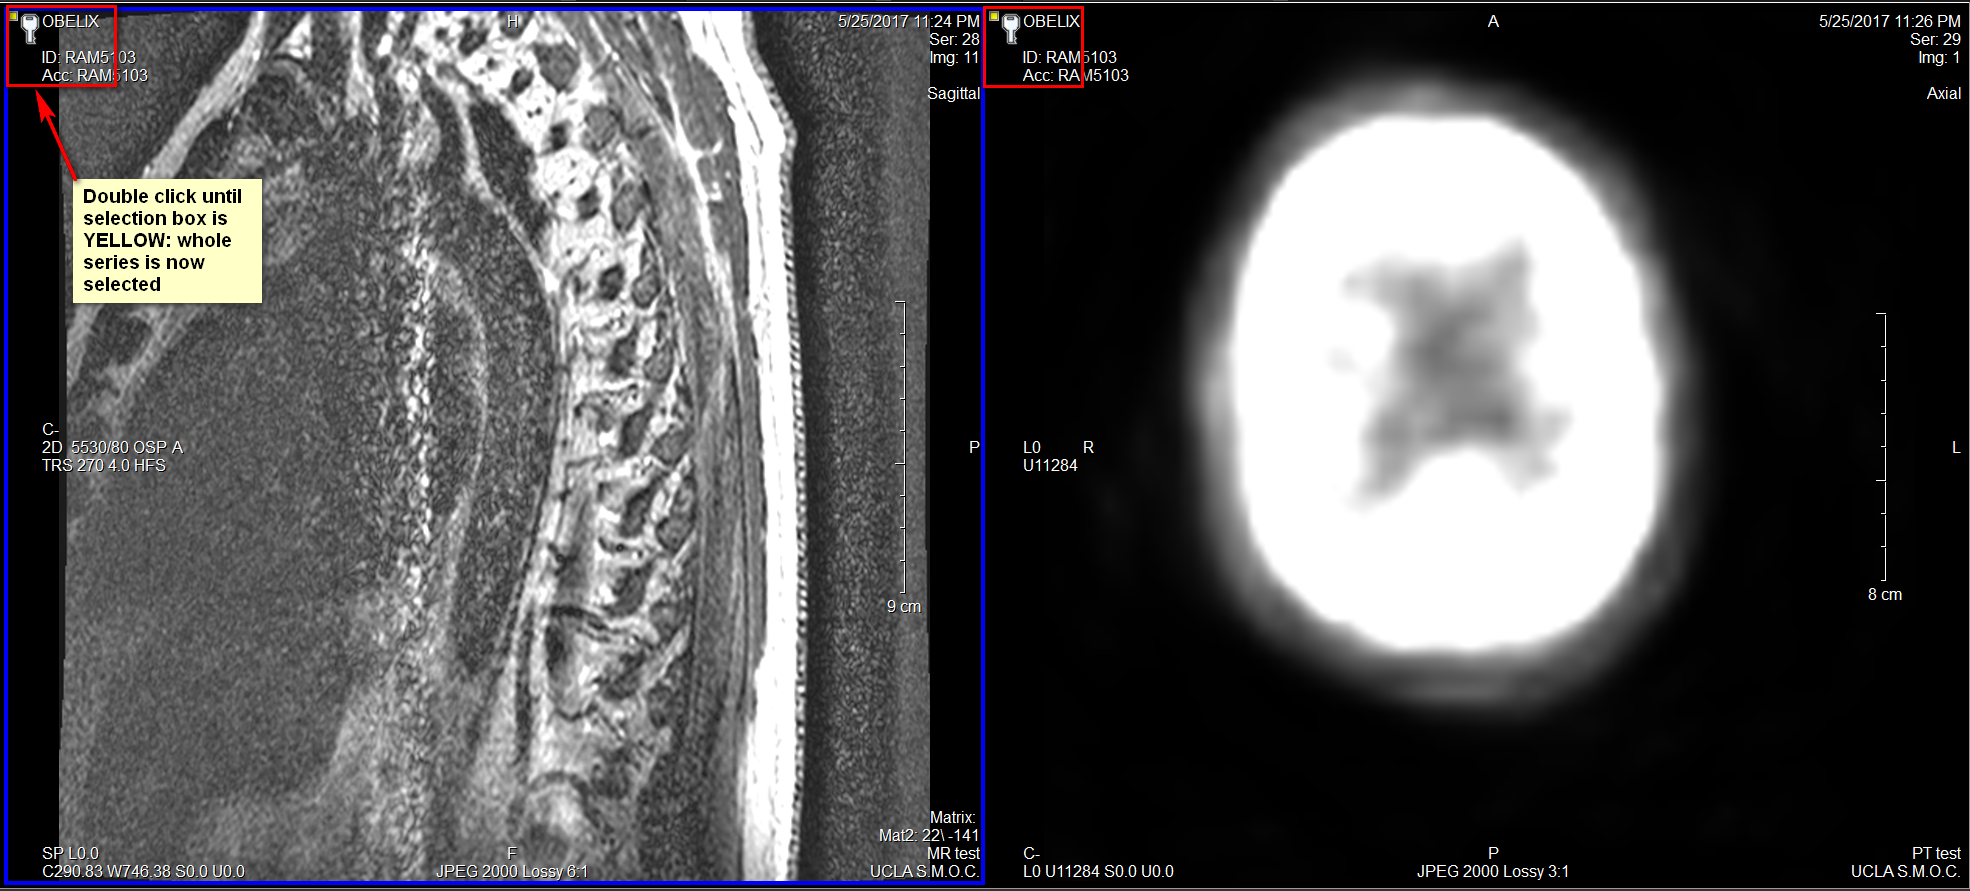

To select all images in the Series for print, double click on the selection box until it is yellow.